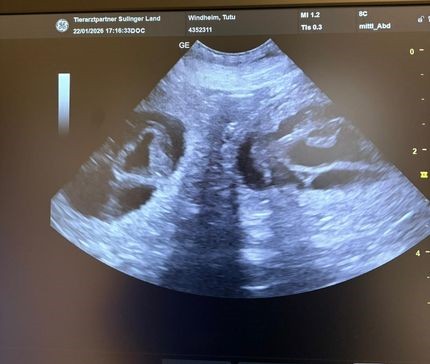

Heute haben die Auswertung von Hetties HD-Röntgen bekommen. Die Ergebnisse sind nahezu perfekt:

HD A2    ED 0    OCD bds.frei  LÜW 1

Wir freuen uns sehr, damit stünde einer möglichen zukünftigen Zuchtverwendung von Hettie nichts im Wege.